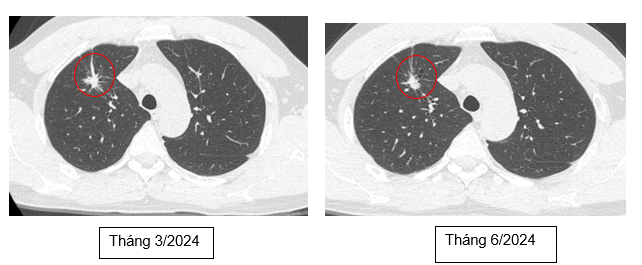

Cắt lớp vi tính ngực: Nhu mô thùy trên phổi phải có nốt tổn thương tỷ trọng tổ chức, kích thước ~ 8x11mm, bờ tua gai, cắt cụt nhánh phế quản phân thùy S3m, giãn phế quản lân cận. Ngoài ra nhu mô thùy trên có vài nốt đặc nhỏ <4mm, giới hạn rõ, bờ đều.

Hình 3: Hình ảnh chup cắt lớp vi tính ngực thấy khối u thùy trên phổi phải giảm kích thướcc còn 11x08 mm, bờ tua gai

Đánh giá điều trị phác đồ ABCP sau 6 tháng: Các triệu chứng lâm sàng được cải thiện, bệnh nhân ổn định, không ho, không sốt, không đau ngực, không sờ thấy hạch thượng đòn

Cắt lớp vi tính ngực: Nhu mô thùy trên phổi phải có nốt đặc bờ không đều kích thước 6x4mm, xung quanh có các ổ giãn phế nang và các dải xơ co kéo nhẹ nhu mô phổi, hạn chế đánh giá tính chất ngấm thuốc do kích thước nhỏ. Ngoài ra nhu mô thùy trên có vài nốt đặc nhỏ <4mm, giới hạn rõ, bờ đều. Không thấy giãn phế quản - phế nang.

Hình 4: Hình ảnh chup cắt lớp vi tính ngực thấy nốt đặc trên phổi phải kích thước nhỏ 06x04 mm

Nhận xét: Như vậy theo tiêu chuẩn đánh giá đáp ứng khối u RECIST 1.1, bệnh đáp ứng một phần. Trên các phương tiện đánh giá hình ảnh như chụp cắt lớp vi tính ngực, bụng, cộng hưởng từ sọ não không thấy tổn thương bất thường nghi ngờ thứ phát. Về mặt lâm sàng, bệnh nhân hoàn toàn ổn định, không sờ thấy hạch cổ, hạch thượng đòn, xét nghiệm chỉ điểm u giảm về mức bình thường, ngoài ra bệnh nhân không gặp tác dụng phụ của phác đồ điều trị -> Xử trí: Bệnh nhân chuyển sang phác đồ duy trì Atezolizumab – Bevacizumab mỗi 3 tuần/lần cho đến khi bệnh tiến triển hoặc không dung nạp điều trị.